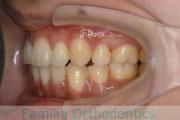

No.22V-211

- 上下顎前突

- 交叉咬合

- 17歳

- 女性

- 抜歯部位

- 上:

- non

- 下:

- 主な使用装置:

- Invisalign

- 治療にかかった費用:

- 90万円

奥歯の歯並び、特に7番のすれ違いを治して欲しいとのことで来院されました。特に左下の舌側への倒れこみが強い、叢生(でこぼこ、ガタガタ)の症例です。マウスピース型矯正装置の一つ、マウスピース型矯正装置のひとつ、インビザライン/Invisalign®(薬機法および医薬品副作用被害救済制度の対象外)を用いて治療を行いました。にて治療を行いました。2年弱、20回程度通院していただきました。インビザラインは、患者さんの使用状況により治療効果が上下してしまうリスクがあります。